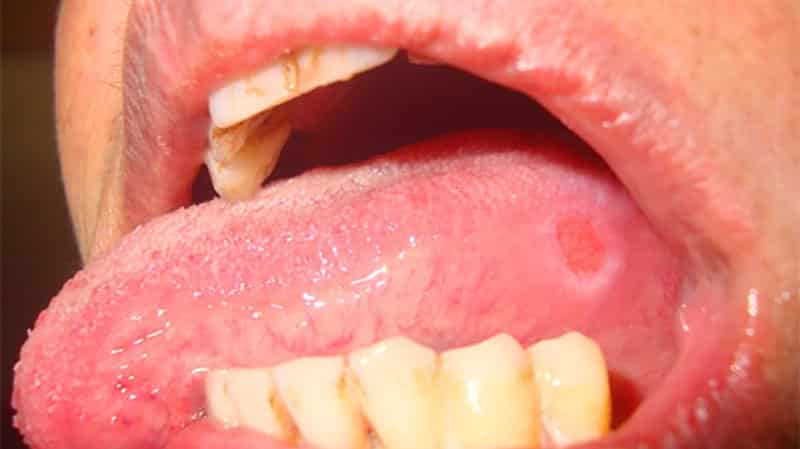

Что на счёт внешнего вида

Количество язвочек может варьироваться, как и их внешний вид. Иногда наблюдается всего одна язва, а в других случаях воспалительные процессы охватывают всю ротовую полость. В начале она выглядит как небольшая опухоль с красноватым оттенком. Затем на её поверхности образуется белесая плёнка. Такие воспаления, как афтозный стоматит или простой стоматит, характеризуются именно белым цветом. При обращении к врачу, скорее всего, вам поставят именно этот диагноз.

Даже если появилась всего одна маленькая опухоль, лечение следует начинать без промедления. В противном случае она может прогрессировать, и вскоре появятся новые образования.